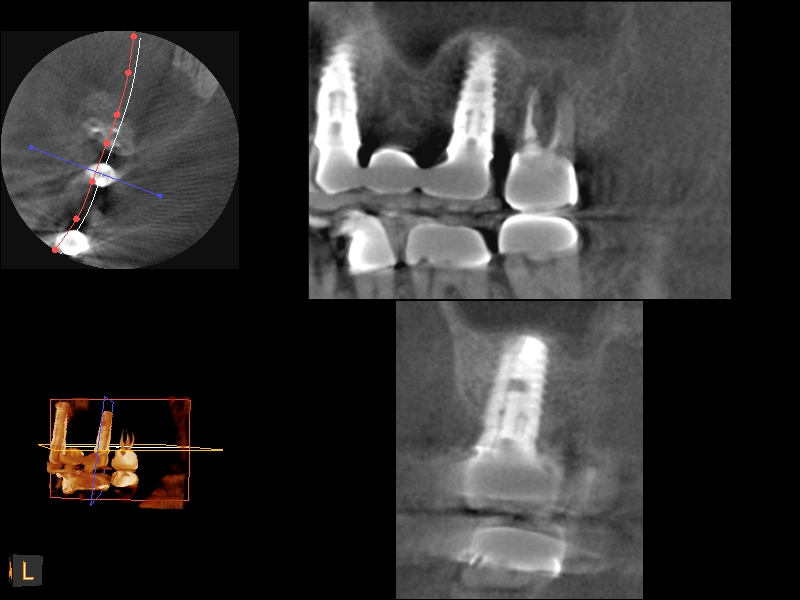

A 4-month CBCT scan (Kodak 9000D) of

implant No. 14.

Fig. 7

Because the bone grafting materials used in this technique need physical stability during healing to support the raised membrane, there is a high probability that significant shrinkage of the graft will occur as it heals and matures if only non-demineralized material is used. For these reasons, a composite graft using calcium sulfate, DFDBA, and mineralized particulate bone is used. A 50:50 mixture by volume of mineralized bone grafting material and DFDBA is used, to which approximately 40% calcium sulfate by volume is added. A higher percentage of calcium sulfate is used relative to that described for composite grafting in other uses, because some of the calcium sulfate will wash out during bone packing. Another advantage to this composite graft is that it is not as radiopaque as a purely mineralized graft. This allows radiographic monitoring of the bone healing around the implant, which can be used to time abutment placement on the implant. This is demonstrated in Figure 4 and Figure 5, which are radiographs taken on the day of the initial surgery showing the radiographic appearance of the composite graft, implant, and graft, and in Figure 6, a 5-month postoperative radiograph with the abutment in place. The old floor of the sinus is indistinguishable from the area of new bone. Figure 7 shows a CBCT scan (Carestream Dental, www.carestreamdental.com) taken at 4 months with the old floor of the sinus indistinguishable from the new bone formed.

The implant is then delivered and should be well stabilized in the bone. If there is any mobility of the implant, it can either be placed a little deeper (if there is enough native bone) or the implant can be removed and the procedure aborted, in which case it would be a two-stage procedure. This should rarely occur with the tapered designed implant, even with only 2 mm of native bone. Using a bone-level platform-shifting implant (or a tissue-level designed implant) is critical, as the hard and soft tissue will establish a biologic width. If an external hex type of implant is used and the shoulder is placed at the bone level, an expected bone loss of 1.5 mm to 2 mm will occur.24 Figure 10 shows proper bone-level implant depth placement with a platform-shifting design. In this case, a 3-mm healing abutment was placed at the time of surgery to avoid a secondary uncovering surgery, but an implant-level healing abutment could have been placed instead. As can be seen, there was only about 2 mm to 3 mm of native bone height. The membrane was raised about 8 mm to 9 mm. Comparing the radiograph on the day of surgery (Figure 10) to the 6-month postoperative radiograph (Figure 11) shows no loss of native bone, as well as the positive change in appearance of the grafted bone. The 3.5-month CBCT scan (Figure 12) shows good healing of the bone with no coronal bone loss. With minimal native bone present, as in this case, the use of a non-platform-shifting or non-tissue-level implant design could be problematic. After 1.5 mm to 2 mm of crestal bone loss, an external hex designed implant could develop instability with possible implant failure. If a non-tapered implant is used and bone loss occurs during healing, migration of the implant into the sinus could potentially occur. The surgeon can use either a healing abutment or implant-level closure screw over the implant shoulder. With patients who tend to use their tongues to explore or play with the area, or if the area is under a removable partial denture, a closure screw is recommended.